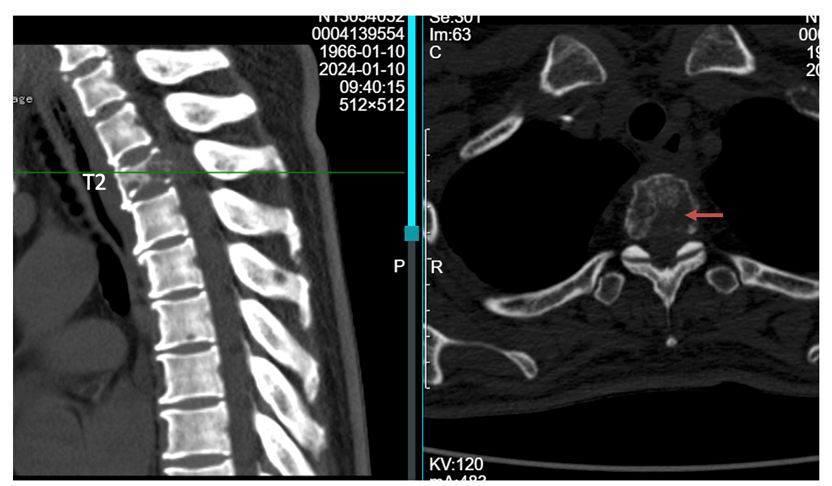

读片:CT及MRI检查提示,T2,L2,L5椎体骨质破坏,红色箭头所指为转移病灶所在位置,可见L2椎体病灶已侵犯后壁,突入椎管内。